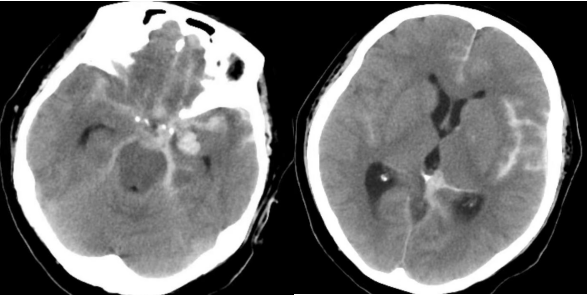

患者女性,62岁。既往有高血压病史及冠脉支架置入史。来院前突发剧烈头痛,伴恶心呕吐,抽搐一次。就诊于北京市垂杨柳医院急诊科,行头颅CT检查提示蛛网膜下腔出血,当即请神经外科会诊。神经外科医生段练第一时间赶到急诊,查看患者呈嗜睡状态,颈项强直。紧急为患者安排了头颈动脉CTA检查,CTA显示左侧后交通动脉瘤。动脉瘤不规则,再出血风险极大,再出血后果不堪设想,需尽早手术治疗。

▲术前头颅CT显示广泛蛛网膜下腔出血